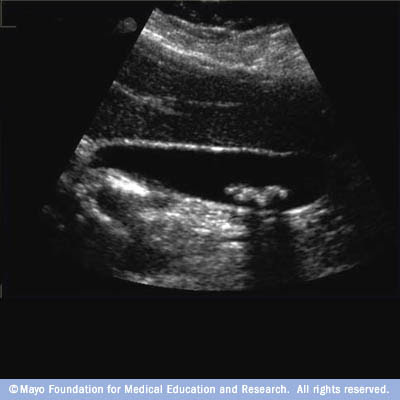

Gallbladder And CBD - LAPSF

Ultrasound showing 2 large gallstones within the gallbladder. Notice how they These pictures illustrate how the flexible scope is able to remove stones from the duct. Catheters Gallbladder and CBD Author: ... Return Document